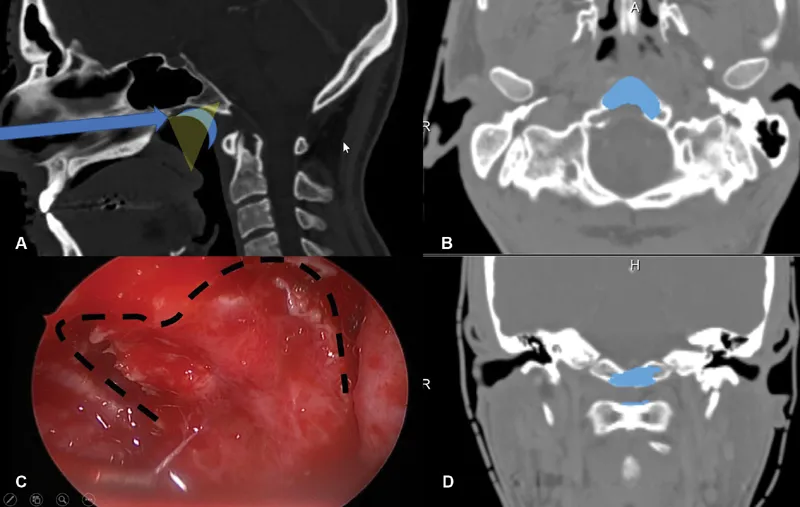

上图术前术后影像资料对比,术前(红色箭头):图A、B显示了下斜坡及齿状突可见中线占位病变,影像学表现为脊索瘤侧伸有限。术后(蓝色箭头):图C、D显示了用于闭合瘤腔的脂肪移植物,没有肿瘤残留。术后MRI显示完成了肿瘤全切除。术后患者无神经功能缺损。病理检查显示为典型脊索瘤。

▼术中情况:术中通过磁共振成像(MRI)监测术后神经功能缺损和术后肿瘤体积。在鼻内窥镜下以30度和45度角行双鼻孔入路。随后,制作一个心形皮瓣,钻取斜坡以暴露病变(图2)。在初始减压后,轻轻钻取C1环以到达齿状突内及周围的肿瘤,并进行完整切除。